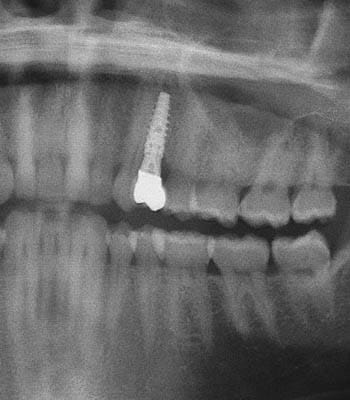

Single Tooth Replacement